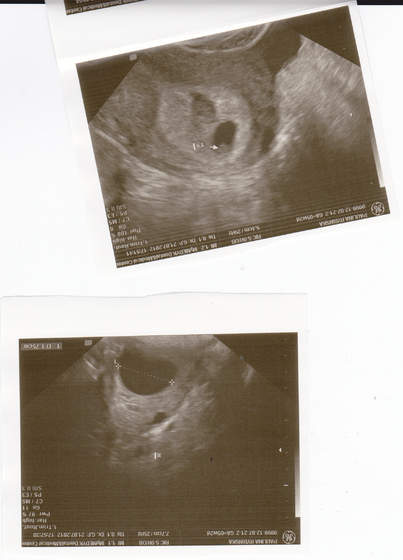

Skoro masz starego krwiaka to musialaś krwawić, albo brudzić (taki brązowy sluz). Wszystko zależy od tego gdzie umiejscowiony jest krwiak. Ja miałam przy samym ujściu, więc krwawilam non stop, bo on sie wydalał. Krwiak sie wchłania wraz ze wzrostem dziecka. Narazie Kruszynka jest zagrożona, bo jest za malutka. Dziwie sie, ze lekarz nic ci nie przepisał, bo przy krwiakach trzeba brać leki. Może on w ogóle nie ma pojęcia i możesz nie miec krwiaka. Widziałaś go na usg? Jakąś czarną plamę wokół zarodka?